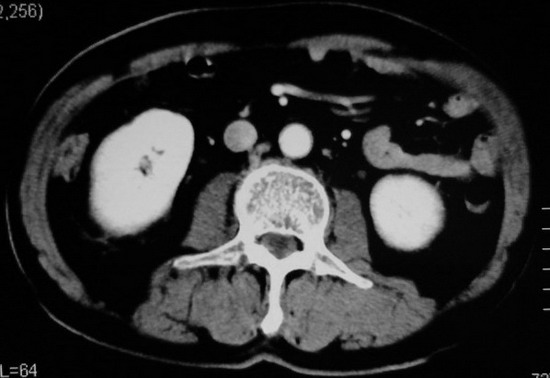

以下是引用杀毒软件在2008-11-17 19:15:00的发言:[br]考虑------右肾癌合并肾静脉---同侧肾上腺受侵可能性大

以下是引用zjzjr在2008-11-17 20:45:00的发言:[br]考虑------右肾癌合并肾静脉---同侧肾上腺受侵可能性大及腹膜后淋巴结转移.